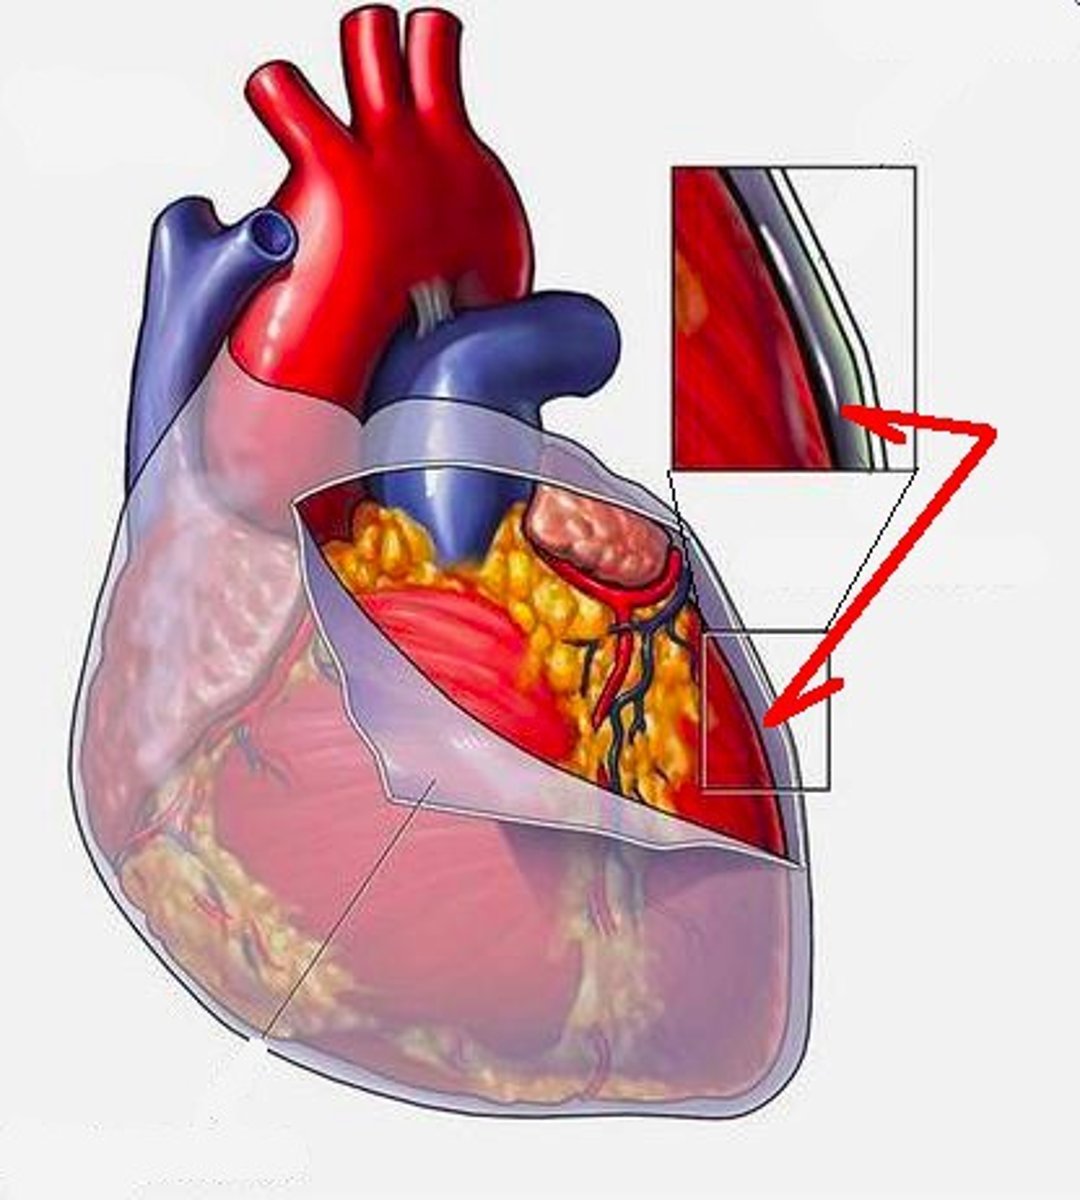

parietal layer of serous pericardium

layer on the backside of the fibrous pericardium

D

visceral layer of serous pericardium

layer directly on the heart

E

H4

Pericardial cavity

probe between the 2 layers

endocardium

Layer; layer inside the donut

cross section with circle

Myocardium

Layer; thick band, middle of donut

Epicardium

Layer; most superficial, cross section with circle